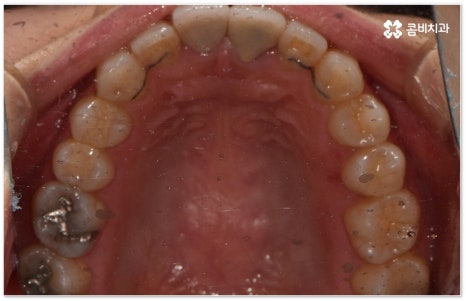

희고 가지런한 치아를 드러내며 환하게 웃는 사람을 보면 자기도 모르게 호감이 가곤하죠, 이처럼 대인 관계에서 치아는 좋은 인상을 만드는 데 심미적으로 큰 역할을 할 뿐 아니라 식사시 음식물을 저작하고 발음을 제대로 하는 데도 많은 도움을 주기 때문에 만약 타고난 치아가 삐뚤어졌거나 위아래 교합이 제대로 맞지 않는다면 이를 기능적 심미적으로 바로잡아 주기 위해서 치아 교정 치료를 고려해 볼 수 있습니다.

특히 업무적으로나 생활적으로 대인 관계가 활발하신 중장년 성인분들의 경우 치료 기간이 너무 오래 걸리지 않는지, 치아교정장치 가 너무 눈에 띄지는 않는지 궁금해 하시는 경우가 많이 있는데요. 말씀드렸던 것처럼 기술이 발달하면서 다양한 치아교정장치 가 나와있고 치아교정장치 자체는 결과에 크게 영향을 주지 않으므로 몇몇 케이스를 제외하면 환자분들께서 중요하게 생각하는 바 (심미성, 합리성 등) 를 반영할 수 있는 여지가 많이 있기 때문에 숙련된 의료진과 충분히 상담하셔서 각각의 장단점을 잘 살펴보시고 자신에게 꼭 맞는 장치를 고르시면 되니 크게 걱정하실 필요는 없을 거예요.

요즘 가장 많이 쓰이는 치아교정장치 인 클리피씨는 치아 색상의 세라믹 브라켓을 이용하기 때문에 심미성도 뛰어나고 자가결찰방식을 이용하여 보다 적은 힘으로 지속적이고 부드러운 치아 이동을 할 수 있도록 고안된 장치이므로 통증을 줄여줄 뿐 아니라 보통 2년 남짓 걸렸던 전체 교정 기간 역시 6개월 정도 감소시켜 줄 수 있습니다. 환자분들의 상황에 따라 내원 횟수 역시 줄일 수 있기 때문에 업무가 많이 바쁜 직장인분들의 경우에도 이용할 수 있다는 장점을 가지고 있어요.

이때 환자분들의 상황에 따라서 구조적인 원인이 크지 않고 교합이 심하게 어긋나지 않은 상태에서 치아의 각도만 살짝 앞으로 튀어나와 있거나 사이가 조금 벌어져 있는 등 부분 교정으로 치열을 가지런하게 바로잡을 수 있는 케이스도 있는데 이런 경우 6~8개월 정도의 보다 짧은 기간에 간편하게 치료를 끝낼 수 있으니 먼저 꼼꼼한 검진을 통해 자신이 부분 교정이 가능한지 여부를 알아보시면 좋을 거예요.

부정교합을 개선할 때 교합이 어긋난 정도가 심하고 구조적인 원인이 커서 부분 교정이 아닌 전체 교정이 필요한 케이스인 경우라고 해도 말씀드렸던 클리피씨 교정 장치 또는 보다 심미성을 강조한 치아교정장치 들의 도움을 통해 다른 사람과 얘기를 하거나 음식을 먹을 때 브라켓이 두드러지게 드러나는 부담을 줄일 수 있으니 설측교정, 콤비교정, 투명교정, 인비절라인 등에 대해서 한 번 알아보시고 각자에게 맞는 방법으로 교정 치료를 시작해 보시길 권유드리고 있어요.